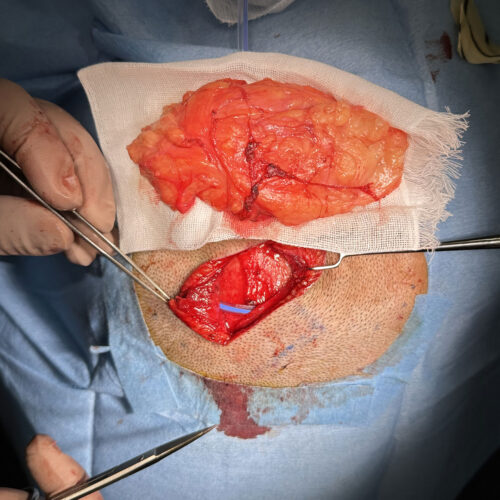

術中所見①

脂肪腫を丸ごと完全に取り出し、その下にはドレーンと言って管を挿入留置します。

術中所見②

摘出した脂肪腫はかなり大きく12cmを超えるものでした。